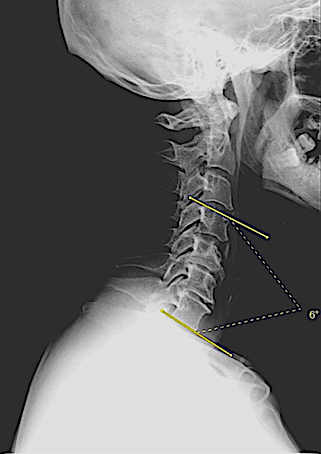

En mi opinión, las cajas intersomáticas atornilladas (CISA) son la mejor opción para corregir la cifosis cervical anterior, especialmente en patología multinivel. Además, a diferencia de «Cage Stand Alone» o caja cervical + placa; la lordosis conseguida se mantiene mejor en el tiempo.

En la técnica quirúrgica es clave asegurar una descompresión adecuada y respetar al máximo la anatomía de los platillos cervicales lo que, en algunos casos de espondilosis avanzada, es laborioso.

Aquí presento dos ejemplos.